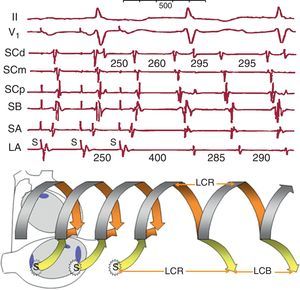

Figura 17. Encarrilamiento de una taquicardia auricular macrorreentrante de aurícula izquierda mediante estimulación en aurícula derecha lateral alta. Se muestran registros de aurícula derecha septal alta y baja y senos coronario proximal, medio y distal. El esquema (abajo) representa el circuito de taquicardia auricular macrorreentrante en la aurícula izquierda desplegado en el tiempo como un helicoide. El frente estimulado (flecha amarilla) alcanza el circuito y lo penetra en dirección ortodrómica y antidrómica en cada ciclo, y al cortar la estimulación el circuito se restablece a su ciclo basal. Los registros muestran la inversión de la secuencia de electrogramas de lateral alta, septal alta, septal baja y seno coronario proximal durante estimulación (S), mientras no cambia la secuencia de seno coronario distal→seno coronario medio (fusión del frente estimulado y el encarrilado en el circuito). Al cortar la estimulación la taquicardia auricular macrorreentrante vuelve al ciclo basal de 295 ms, como muestran los senos coronarios distal y medio, pero en el punto de estimulación (lateral alta) la longitud del ciclo de retorno es más larga porque, al estar fuera del circuito, se añaden los tiempos de conducción hacia y desde el circuito (flechas amarillas). LA: lateral alta; LCB: longitud del ciclo basal; LCR: longitud del ciclo de retorno; SA: septal alta; SB: septal baja; SCd: seno coronario distal; SCm: seno coronario medio; SCp: seno coronario proximal.

Al interrumpir la estimulación de una TAMR, si esta no desestabiliza o interrumpe el circuito, se vuelve a la LC y secuencia de activación basales y la medida de este primer ciclo de retorno tras la estimulación nos permite determinar si el punto estimulado está dentro del circuito (LC retorno=LC basal) (Figura 16) o a distancia del mismo (LC retorno>LC basal) (Figura 17). Esta maniobra es clave para localizar los istmos críticos del circuito y dirigir las aplicaciones de radiofrecuencia durante la ablación.